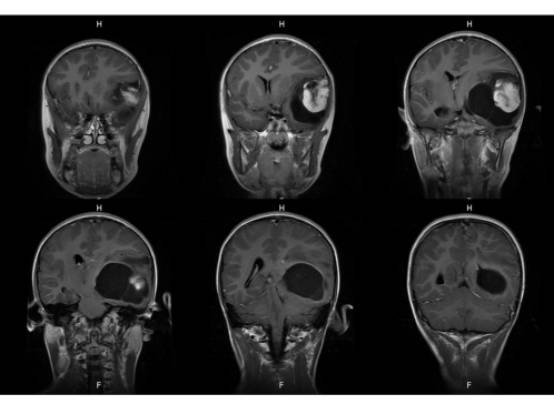

MR平扫及增强示:

MR

左侧颞叶见大块状等长T1等长T2异常信号,FLAIR呈高新,DWI(b=1000)实质部分呈稍高信号,ADC实质部分呈等信号,边界尚清,周围脑实质受压。注入GD-DTPA后病变实质部分呈明显强化。

结果7例肿瘤均位于颅内脑外,单发,体积较大,边界清楚,可见分叶,T1WI示肿瘤呈等信号或稍高信号,T2WI呈等信号或稍高信号,FLAIR呈稍高信号,DWI呈不均匀低信号,CT呈稍高密度影,增强扫描肿瘤实体性部分显著强化,内可见斑点、片状囊变或坏死区;4例可见脑膜尾征,肿瘤内及周边见血管流空或强化血管倍号; 瘤周水肿随肿瘤增大而明显;结论颅内血管周细胞瘤(HPC)是一种少见颅内脑外肿痫,肿痫形态不规则,边缘有分叶,增强扫描显著强化,内均可见斑点、片状囊变、坏死无强化区,瘤内无钙化,肿瘤周边可见血管流空信号,肿瘤恶变时,可见大片坏死出血,肿痛可侵犯破坏周围脑组织和骨组织,但无骨质增生。